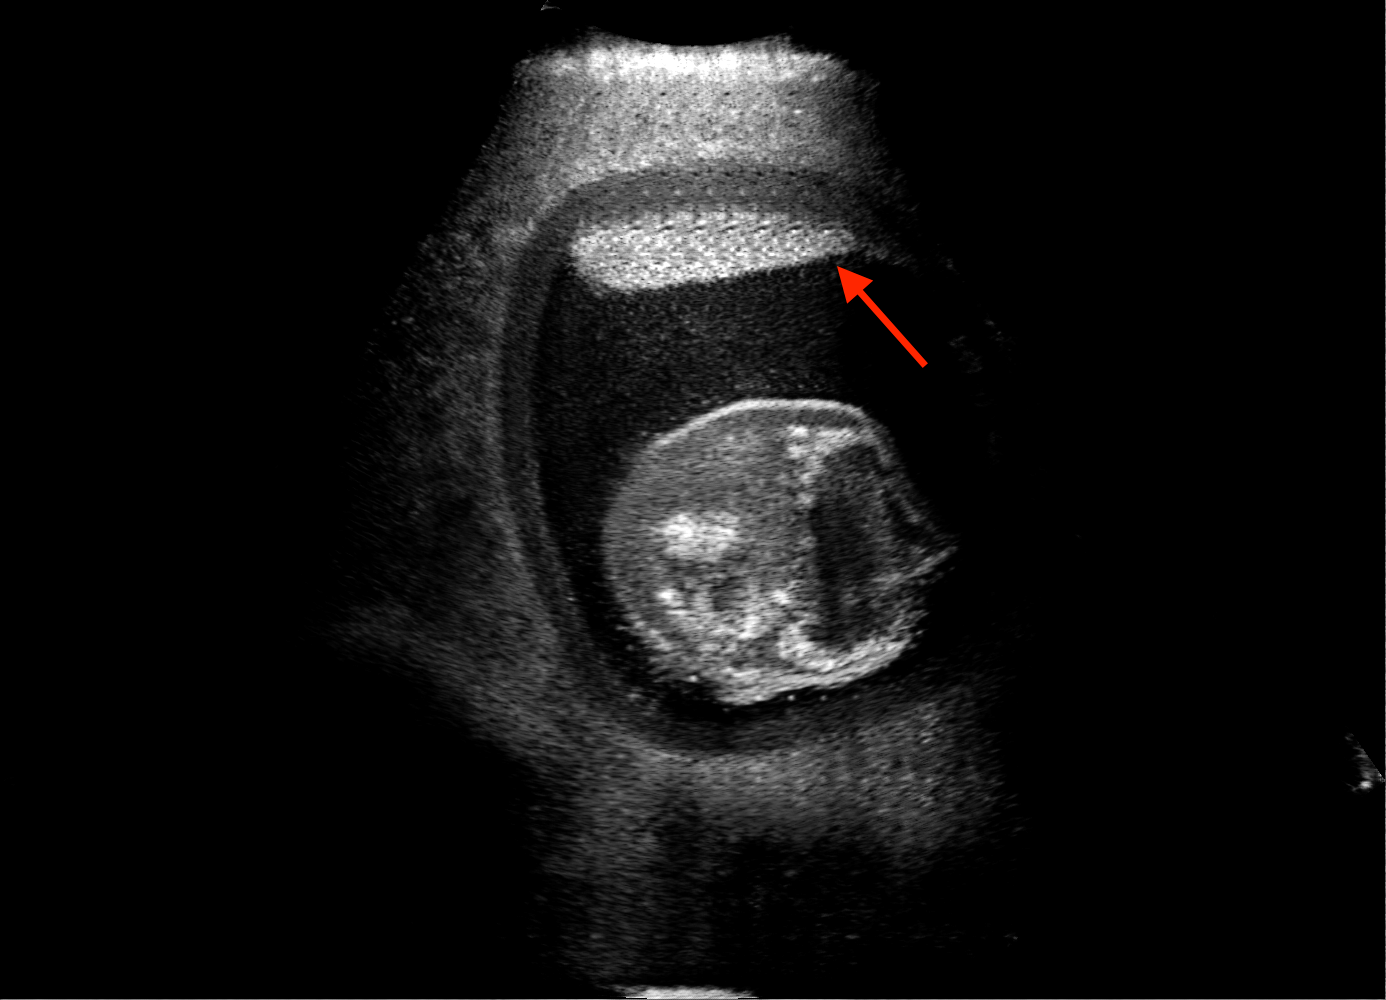

For the interpretation of the local errors, sample spatial p error maps are depicted in Fig. 3 for LSA2H, NSA2H, and SA2H for the middle two examples shown in Fig. 2. Both images generated by NSA2H have a lot of missing structures and accordingly have high error almost all over the map. Artificial skull enhancement with LSA2H is seem to evoke large p error, as shown in the corresponding error map, whereas the bright spots in the error map of SA2H reflect some hallucinated shadows and structure in the brain. All of above mentioned regions of interest are marked by red arrows. In the bottom example, SA2H fails to generate faithful content at the bottom region marked by red circles, which is well indicated by the error map as well.

Fig. 2 depicts the qualitative results for all the models mentioned above, with arrows pointing at structures relevant to discussion points below. The visual results of the ablated variants of SA2H show substantial quality degradation compared to the full SA2H model, demonstrating the importance of each proposed architectural contribution. Given only segmentation map in the network input, SA2H-att fails to generate acoustic shadows, e.g. those cast by the ribs. Detailed structures such as the cervical vertebrae are blurred out in the SA2H-concat results, which also contain hallucinated structures mainly due to insufficient preservation of input information along the encoding-decoding path. With SA2H-conv, checkerboard artefacts are observed due to the lack of proposed additional stride-1 convolutional layers. SA2H-noise without any explicit noise input is seen to be sub-optimal at generating textural details. The baseline method NSA2H fails to preserve anatomical structures and acoustic shadows in all cases, while the simulated textures also show significant artefacts such as checkerboard patterns. Realism of different simulation aspects may become relevant given different clinical applications and scenarios. For instance, improved structural preservation, e.g. with the hyperechoic bony structures such as the skull and the ribs, of the final model over its ablated variants and NSA2H may prove relevant in fetal head measurements, while the textural improvements facilitating screening fetal organ maturity, e.g. lungs. Compared to the silver-standard model LSA2H with a low-quality rendered image as additional input, SA2H is seen to be on par in structural preservation. Note that shadowing on homogenous regions (e.g. the rib shadowing on the homogenous lung region on the 4th column of Fig. 2) with our proposed method SA2H is represented more faithfully compared to LSA2H, whereas shadows on structurally complex regions (e.g. the skull shadowing around the heart and surrounding tissues on the 3rd column of Fig. 2) are suboptimal with our SA2H. Therefore, one may have to evaluate our method given particular simulation tasks, e.g. its clinical validity for fetal heart exams. However, even with low quality rendered images, LSA2H leads to artificial enhancements of intensities, lack of acoustic shadows, and low-quality textures especially near the probe, for which SA2H yields satisfactory results as illustrated in Fig. 2.